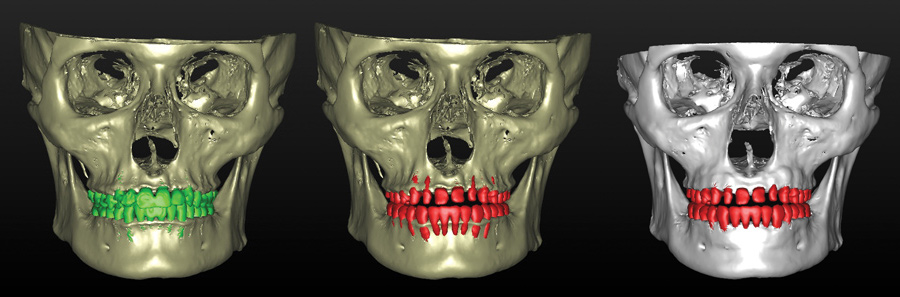

Fig 17. Preoperative 3D CBCT bone and tooth anatomy (left), postoperative tooth position and preoperative bone anatomy (middle), postoperative SFOT bone anatomy and tooth position (right). Note dentoalveolar deficiencies and projected bone loss secondary to tooth movement required to meet restorative goals and dentoalveolar bone deficiencies augmented through SFOT surgery to meet restoratively driven goals.

Figure 17